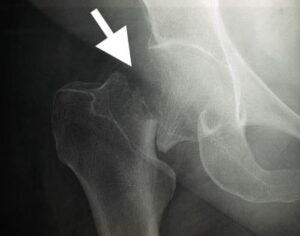

A hip fracture involves damage to one of the four key regions of the upper femur:

- Femoral Neck: Located just beneath the femoral head (the ball), this area connects the head to the shaft of the femur.

- Intertrochanteric Region: This is the area between the femoral neck and the shaft, defined by two prominent bony structures — the greater and lesser trochanters.

Among these, intertrochanteric fractures and femoral neck fractures are the most frequently occurring types of hip fractures. On the other hand, femoral head fractures are exceedingly rare, often resulting from high-impact injuries like car accidents or severe falls.